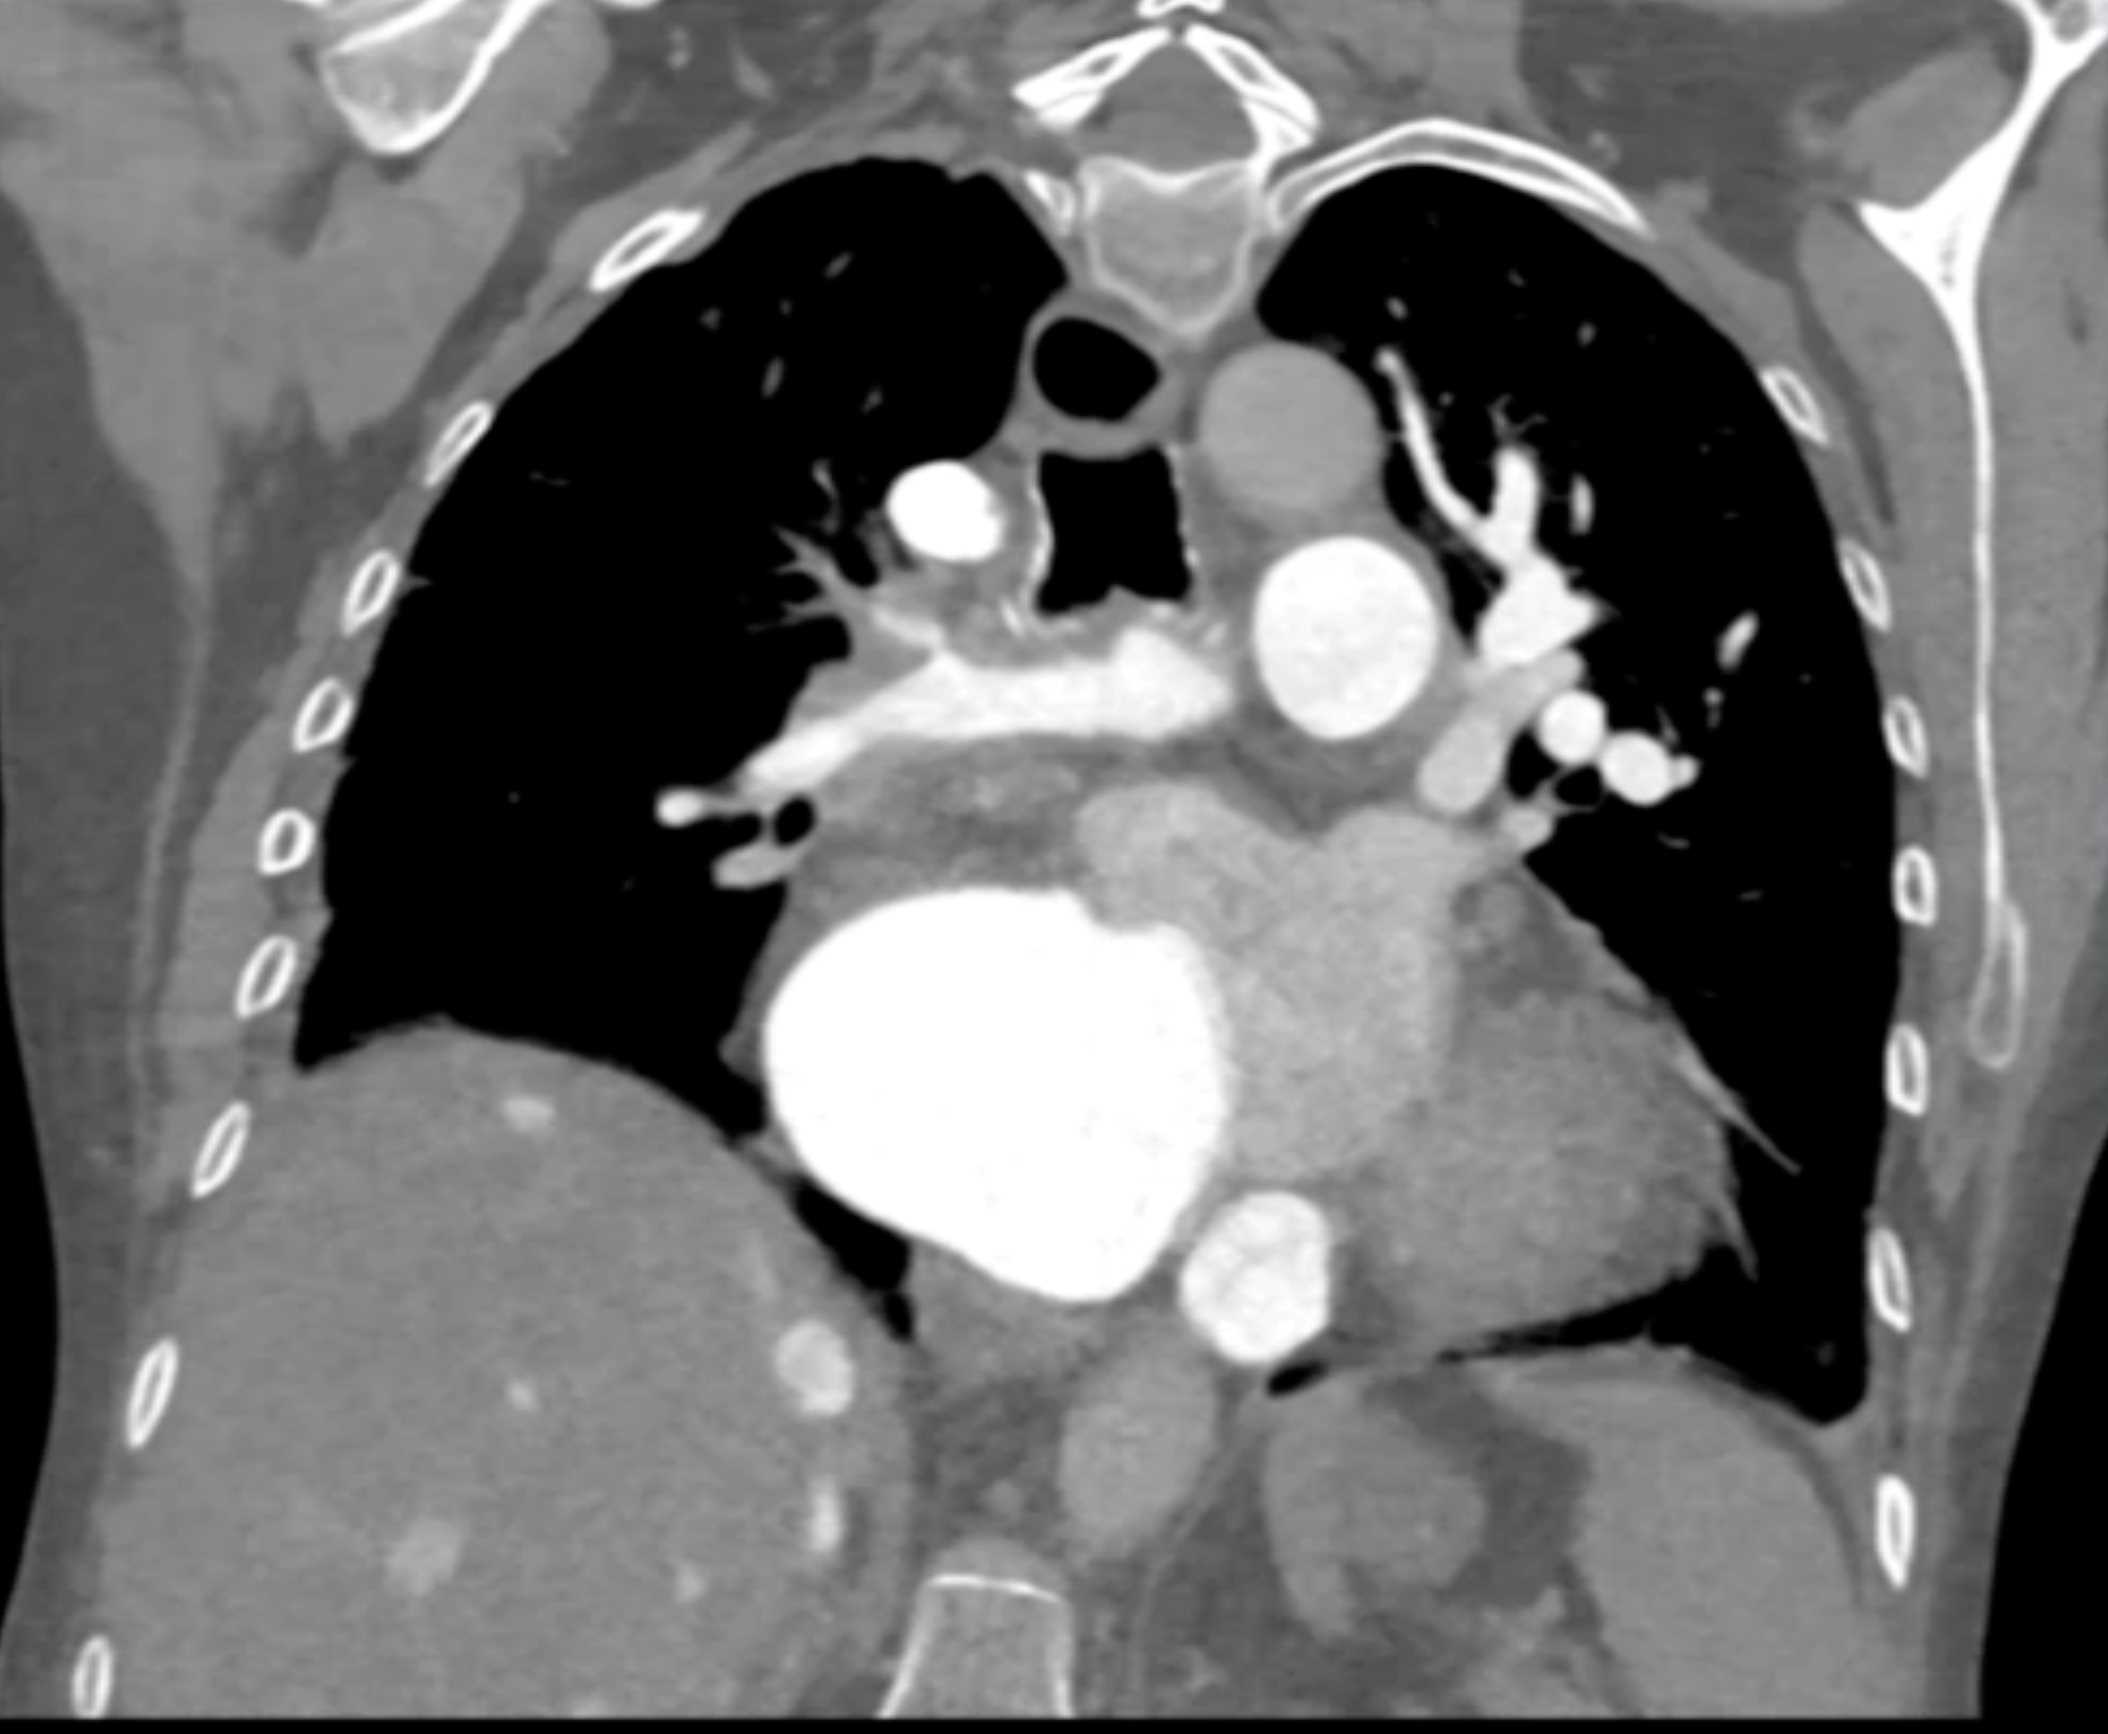

Fibrosing Mediastinitis involves the Pulmonary Artery and Vein